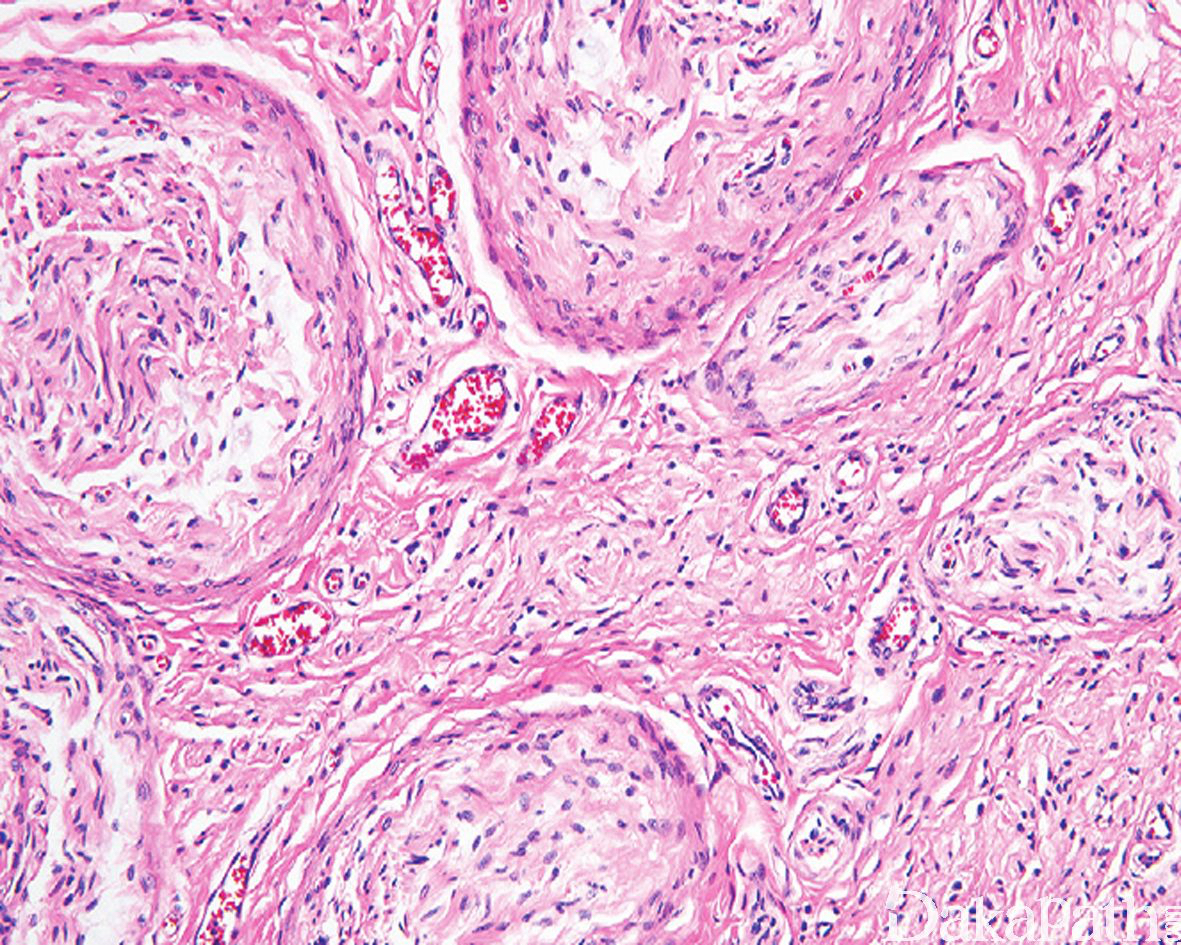

镜下可见丛状排列的、粗细不一的扭曲、膨大的神经束,丛状结节周围可见神经束膜围绕,结节之间亦可见神经纤维瘤性组织伸入;

瘤细胞梭形,核呈波浪状; 间质疏松,血管较丰富,可伴有明显的黏液样变性;

可伴有脂肪成分;